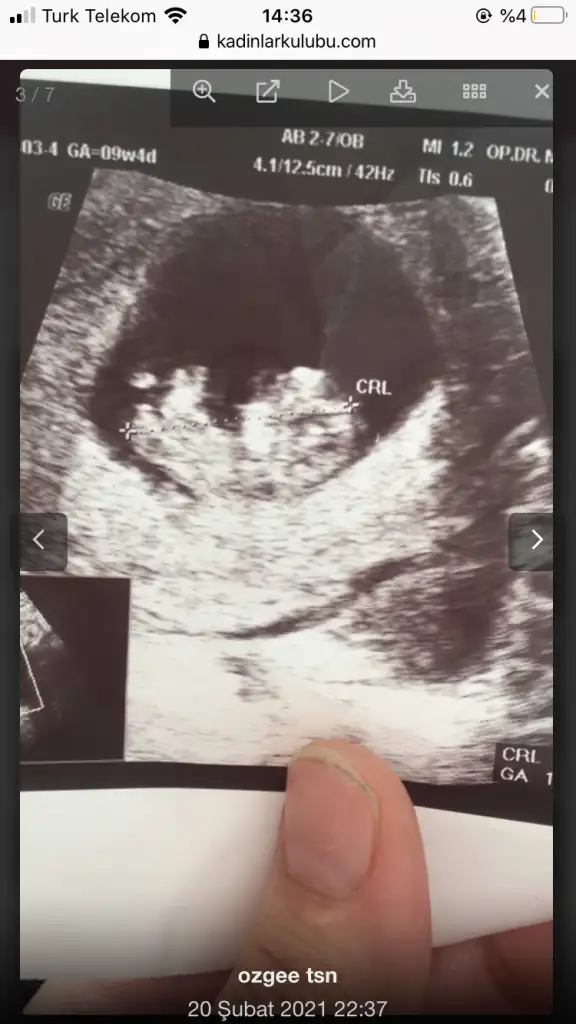

Merhaba 7 hafta 5 günlük burada karından ultrasom abdominal cinsiyet tahmini alabilir miyim bende şimdiden teşekkür ederim.

Ramzi teorisine göre ( bilimsel bir araştırma sonucuymuş ve %85 doğruluğu varmış). İlk 6-8 haftalık ultrason görüntüsüne göre bebeğin kesenin içersinde soldan ya da sağdan girişine göre cinsiyet tahmini yapılıyor. Bilimsel olunca tecrübeli annelerimiz yada anne adaylarımızdan yardım istiyoruz. Doğruluğu var mı öğrenmek adına :) Bizleri aydınlatırsanız çok seviniriz. bu teorieye göre;

Vajinal muayeneyle bakıldıysa eğer;

Sağdan girmiş gözüküyosa aslında solmuş ve ERKEK,

Soldan girmiş gözüküyosa aslında sağmış ve KIZ ,

Karından bakıldıysa eğer,

Soldan girmiş gözüküyosa gerçektede solmuş ve ERKEK,

Sağdan girmiş gözüküyosa gerçekte de sağmış ve KIZ,